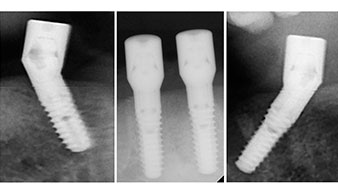

A three-dimensional cone beam computed tomography scan (CBCT, Planmeca) was performed to aid planning and minimize risks. This revealed that the quality and quantity of the available bone were sufficient for the surgery and immediate restoration using the Fast & Fixed method. Following the protocol for this concept, the implants are inserted at 35, 32, 42 and 45. Angling the distal implants by up to 45° shifts the emergence profile to posterior and generates a larger support polygon (Fig. 3).